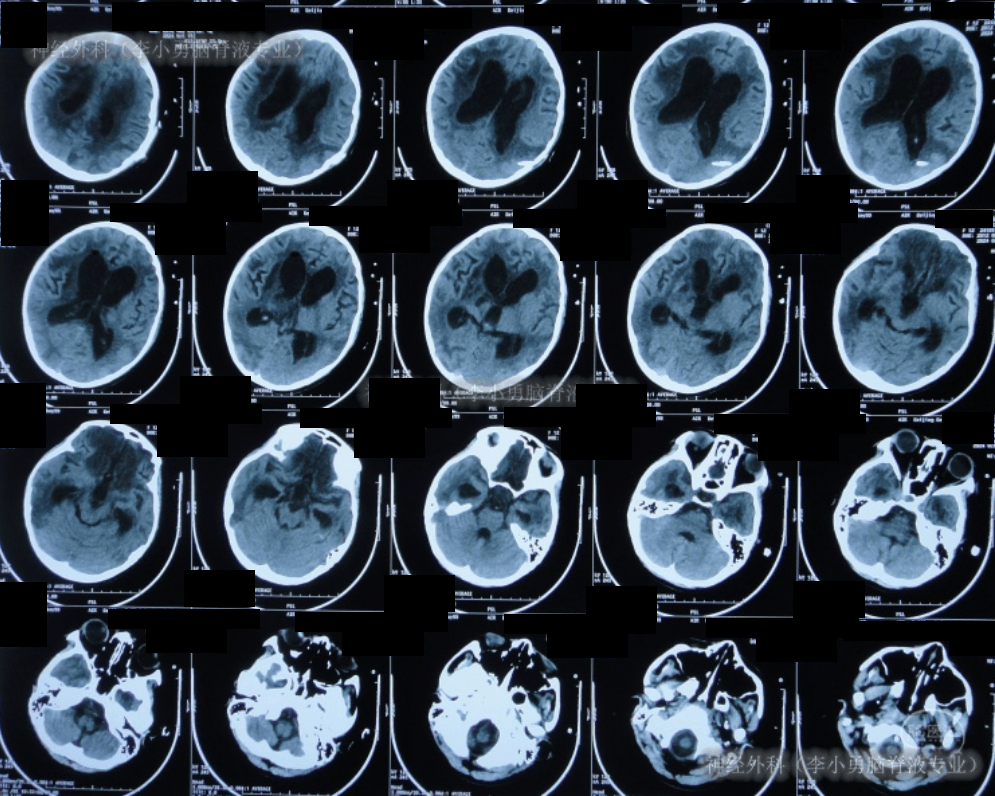

入院时头颅ct示双侧额顶枕叶及颞叶脑损伤,脑室系统扩张,内见点片状

图-6:2024年10月19日头颅ct入院时头颅ct示双侧额顶枕叶及颞叶脑损伤

图-6:2021年1月17日头颅ct脑室外引流5天即2021年1月17日,查头颅ct时

图-9:2022年4月1日头颅ct脑室腹腔分流术后4天即2022年4月1日,查头颅